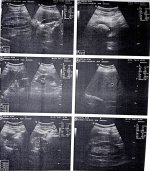

اعانى منذ اول امس من الم فى القضيب عند التبول مع نزول قطرة دم وعدم القدرة على التحكم فى البول وتم عمل اشعة امس الترا سونيك وتم تشخيص بوجود حصوة فى المثانة واخذ مضاد حيوى Ciprofloxacin 500mg قرص كل 12 ساعة وRowatinex كبسولة 3 مرات يوميا وبعد اخذ 3 أقراص من المضاد الحيوى اختفى الدم ولكن مازال عدم التحكم فى البول فى حاله عدم الاسراع الى دورة المياه

فيرجى اعطائى دواء للتحكم فى البول والالم عند التبول ومرفق صورة الاشعه والتقرير

اهلا بحضرتك ، من الاشعة المرفقة اتضح وجود تضخم حميد بالبروستاتا ولذلك ينبغي العرض علي طبيب المسالك البولية لوصف علاج لذلك